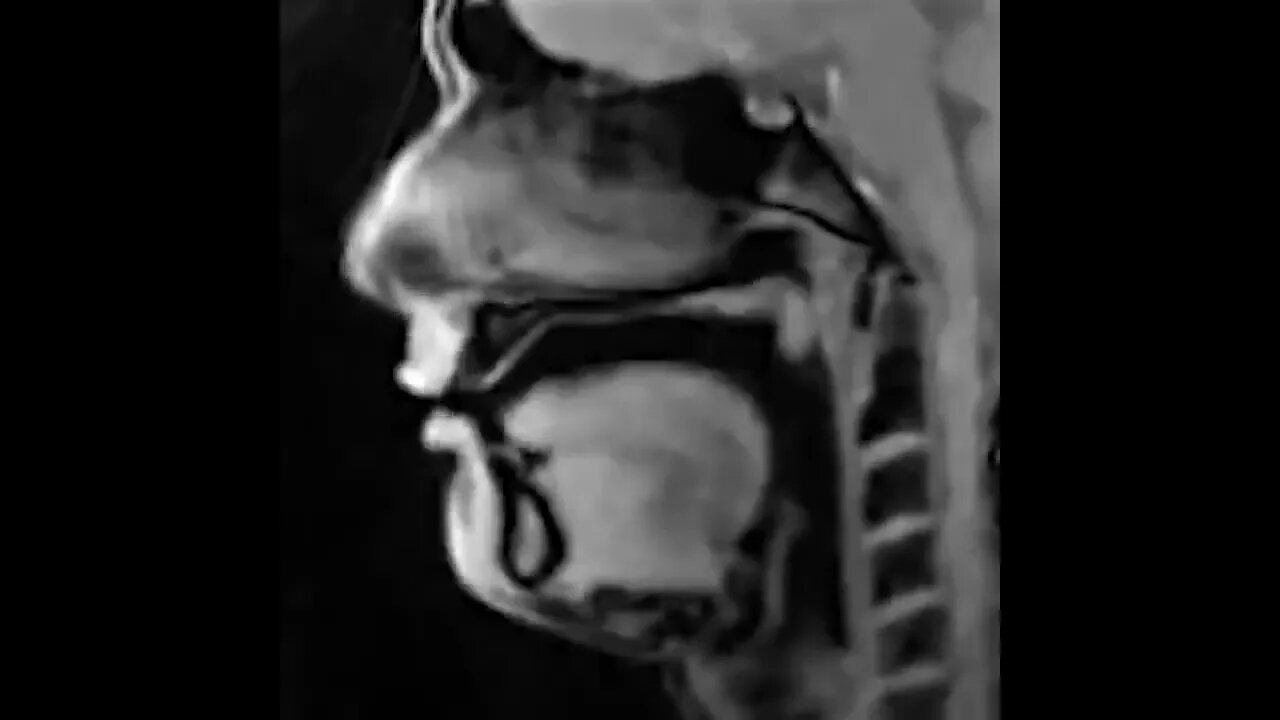

Real-time MRI scan of a person talking.